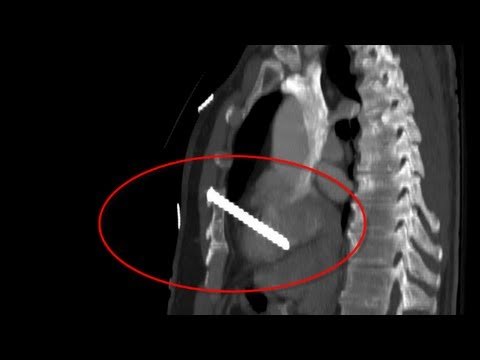

Colorado CEO Richard Talley was found dead in his home in the southern edge of Denver last week after allegedly shooting himself with a nail gun. According to a Denver Post report, the 57-year-old shot himself up to eight times using the power tool. Eight! The whole thing sounded a bit fishy to us here at TomoNews. So we got the expert forensics team at Tomo Labs to look into the matter for us. These trained scientists tested whether or not a human being can exhibit levels of pain tolerance high enough to shoot themselves eight times with an off-the-shelf nail gun. Let's just say they didn't think it was possible. The company that Talley had founded, American Title Services, was under investigation by state authorities at the time of his death, which leads us to believe that something's definitely afoot. Could this all be part of some sick, twisted conspiracy? Welcome to TomoNews, where we animate the most entertaining news on the internets. Come here for an animated look at viral headlines, US news, celebrity gossip, salacious scandals, dumb criminals and much more! Subscribe now for daily news animations that will knock your socks off. Check out our official website: us.tomonews.net/ For news that's fun and never boring, visit our channel: youtube.com/user/TomoNewsUS Subscribe to stay updated on all the top stories: youtube.com/subscription_center?add_user=TomoNewsUS Stay connected with us here: Facebook facebook.com/TomoNewsUS Twitter @tomonewsus twitter.com/TomoNewsUS Google+ gplus.to/TomoNewsUS Instagram @tomonewsus instagram.com/tomonewsus